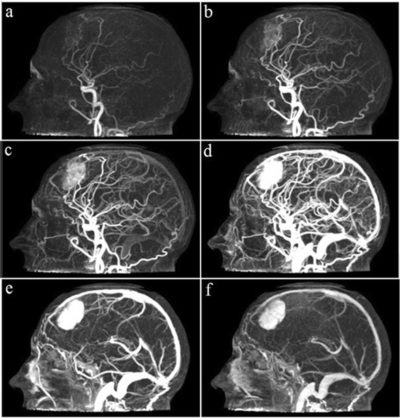

Computed tomography angiography is a computed tomography technique used to visualize arterial and venous vessels throughout the body. Using contrast injected into the blood vessels, images are created to look for blockages, aneurysms, dissections, and stenosis.